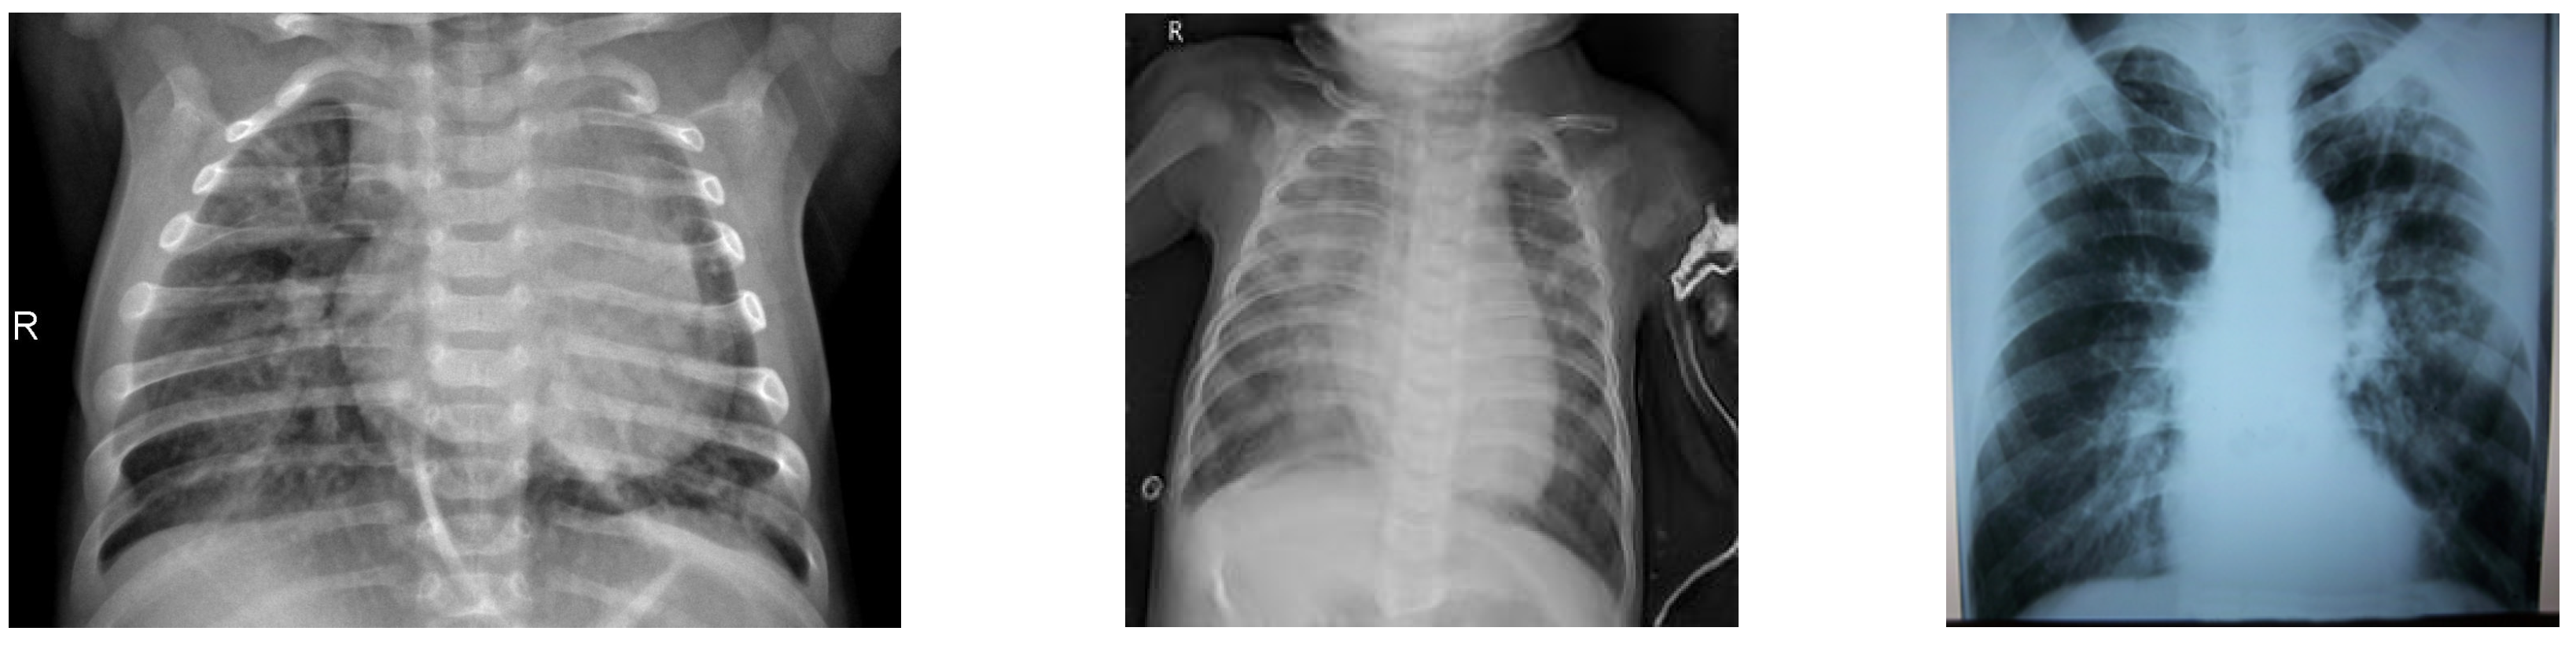

3.1. Dataset

- Chest X-ray Pneumonia. Available online: https://github.com/ieee8023/covid-chestxray-dataset (accessed on 25 January 2022).

- Cohen, J.P.; Morrison, P.; Dao, L. COVID-19 image data collection. arXiv 2020, arXiv:2003.11597. Available online: https://github.com/ieee8023/covid-chestxray-dataset (accessed on 25 January 2022).